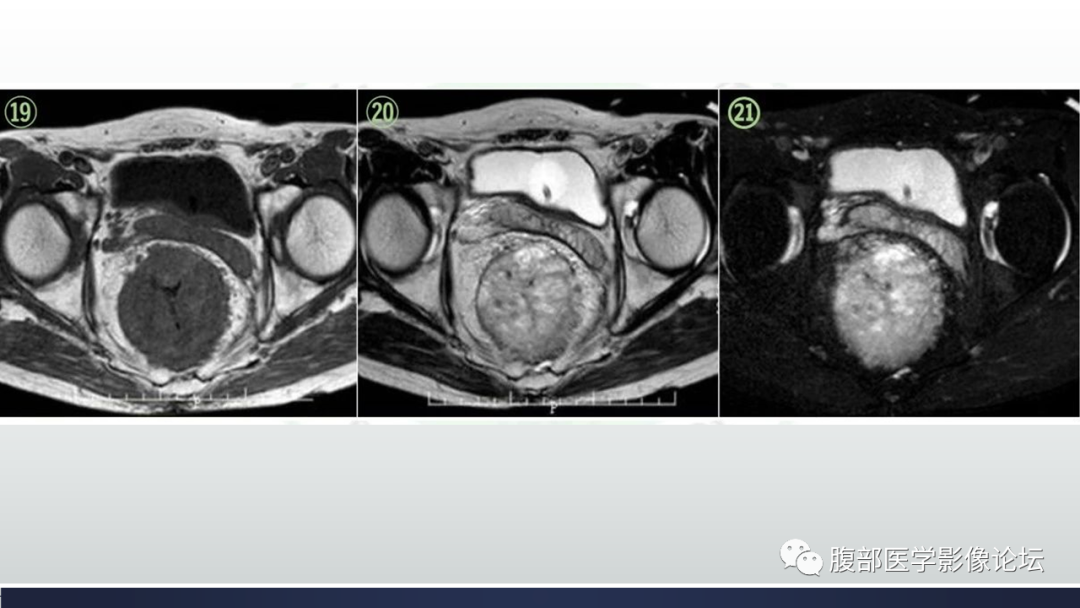

直肠血管瘤1例CT及MR

【病例】直肠血管瘤1例CT及MR-1